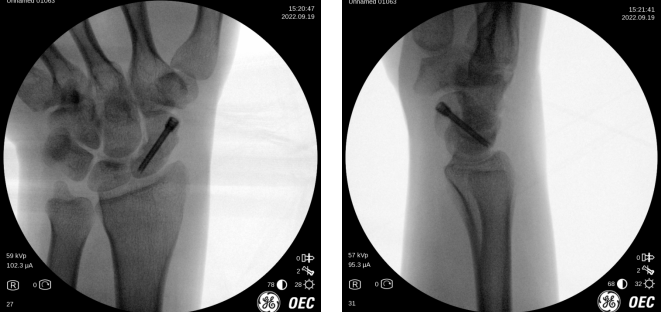

术中摄片